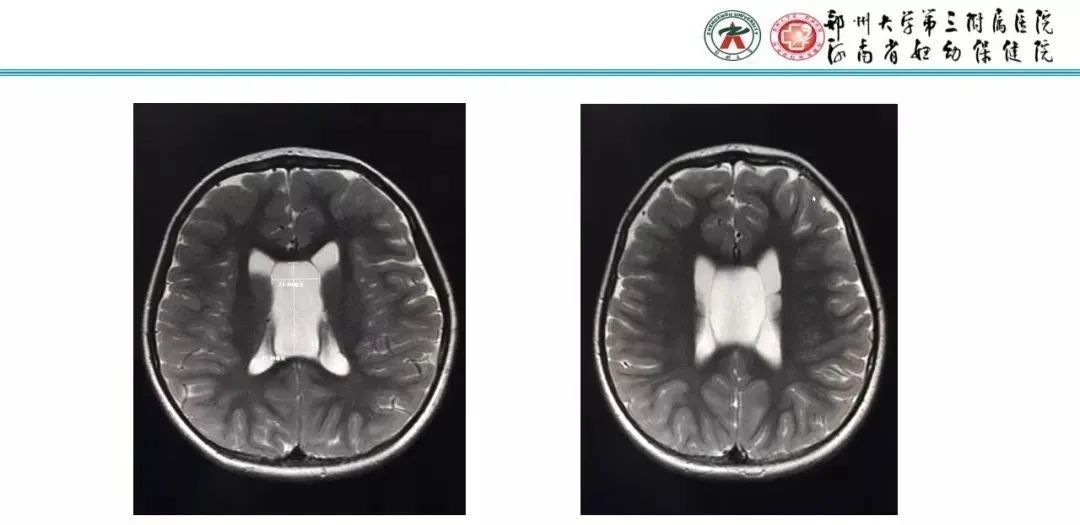

5岁,头痛间断发作1周

【PPT】透明隔腔的影像表现及临床意义-23